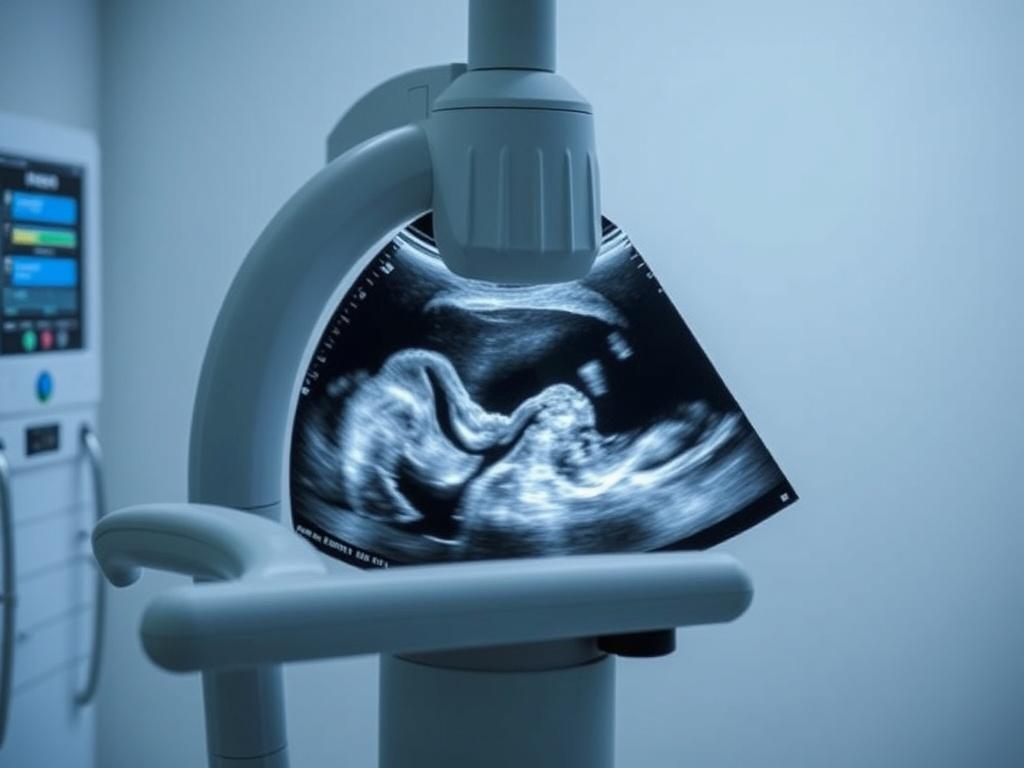

УЗИ в акушерстве |

Плод, плацента, околоплодные воды, матка |

УЗИ при беременности:

- Ранние сроки (1 триместр): наполненный мочевой пузырь.

- Второй и третий триместры: специальной подготовки не требуется.

- У беременных женщин (на любом сроке, в том числе для скрининга плода).